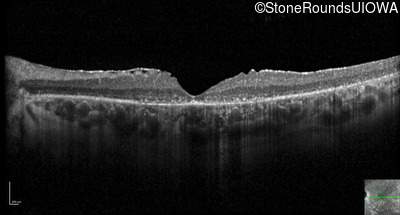

Optical Coherence Tomography - Right - 10/200

Exemplar / OCT Stack

OCT Stack